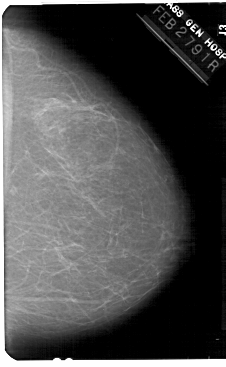

A_1375_1.RIGHT_MLO

RIGHT_MLO LINES 5491 PIXELS_PER_LINE 3706 BITS_PER_PIXEL 12 RESOLUTION 43.5 NON_OVERLAY

FILE: A_1375_1.LEFT_CC.OVERLAY

TOTAL_ABNORMALITIES 1

ABNORMALITY 1

LESION_TYPE MASS SHAPE OVAL MARGINS ILL_DEFINED

ASSESSMENT 4

SUBTLETY 4

PATHOLOGY BENIGN

TOTAL_OUTLINES 1

BOUNDARY